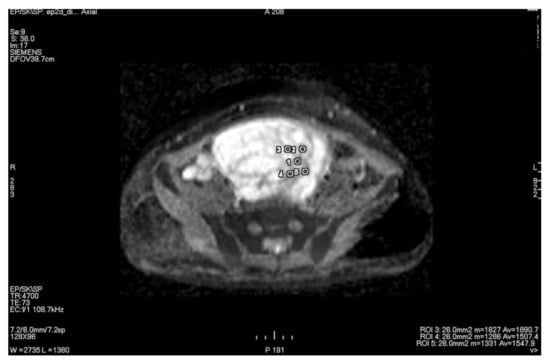

3.1. Primary Tumor DWI

3.2. Inter-Observer Agreement